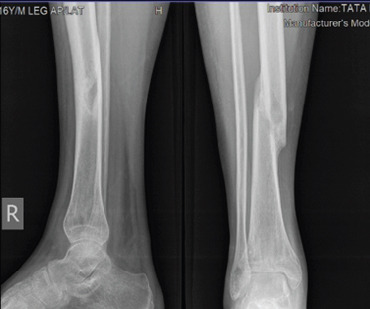

This is a case of a 14-year-old male who sustained a twisting injury to his right leg during early phase of COVID-19 pandemic. He sustained a three-part lateral triplane fracture of the ankle with a concomitant ipsilateral displaced spiral fracture of the shaft at middle-lower third junction of his right tibia (Fig. 1). The mechanism of injury was a twisting injury with external rotation of the foot while running indoors. The ankle injury was initially missed in the emergency. The orthopedic team examined the patient the following morning and ordered a CT scan of the ankle on clinical and radiographic suspicion. CT ankle reported the triplane injury pattern (Fig. 2). The coronal, sagittal cuts revealed 2 mm gap and axial cut revealed 3 mm gap at the articular surface without any step. Conservative plan of management was decided as the displacement of shaft fracture was <50%, varus/valgus angulation <5o, recurvatum <5 degrees and shortening <1 cm and triplane ankle fracture was without any intra-articular step. The patient underwent close reduction under fluoroscopy and above-knee casting (Fig. 3) and was discharged on day-2. Regular follow-ups were done at weekly intervals for initial 3 weeks post-discharge to check for any fracture displacement and then at 6, 10, 14, 18, and 22 weeks, 6 months, 9 months, and 1 year. Above-knee plaster cast was converted to a patellar tendon bearing (PTB) cast at the 10th week for another 4 weeks and weight-bearing was started on PTB cast. The shaft fracture showed abundant callus at 14 weeks and follow-up X-rays (Fig. 4, 5, 6, 7). The triplane fracture was uniting well with no disruption of the tibial plafond (Fig. 8) and an initially open anterolateral physis of the distal tibial gradually closed in the follow-up X-rays. The patient achieved a good functional recovery in 22 weeks and there was no limb length discrepancy at the end of 1 year. Evaluation was done based on modified Weber scale [15] using the pre-operative and post-operative scores for pain, walking, activity, and ankle, subtalar function and awarded clinical demerit points with scores 15/24 at 10 weeks, 10/24 at 14 weeks, 6/24 at 18 weeks, 4/24 at 22 weeks, 2/24 at 6 months, and 0/24 at 9 months.

Figure 1.

Radiographs at presentation.